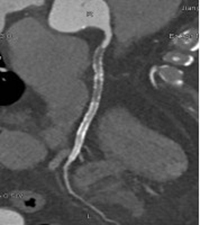

冠脉CTA检查是排查心脏隐患、防范猝死风险的重要手段,也是我们了解自身心脏状况的便捷选择。

检查后,很快就能出具影像诊断结果,清晰呈现心脏血管真实状况,能让隐患无所遁形。

通过冠脉CTA,能清晰地看出多种心脏相关疾病:

最常见的是冠状动脉粥样硬化,也就是常说的“血管变窄”;

还能发现血管内的斑块,判断斑块的大小和稳定性,预警心肌梗死;

还能排查冠脉畸形、血管闭塞等,为临床治疗提供精准依据。